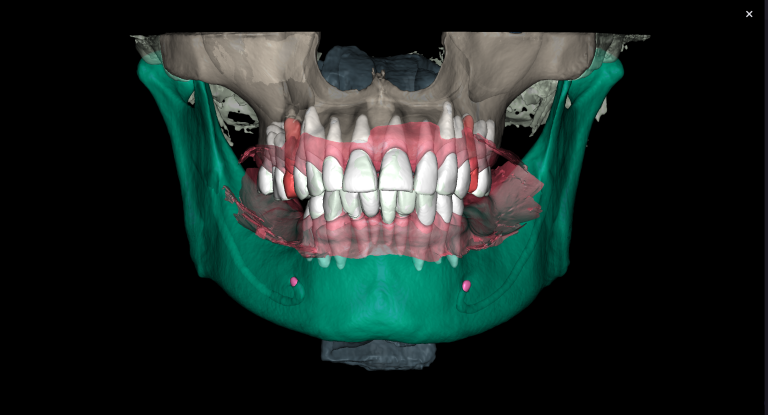

The future gum contour was determined using diagnostic wax-up

Verification of the accuracy of template positioning on the teeth